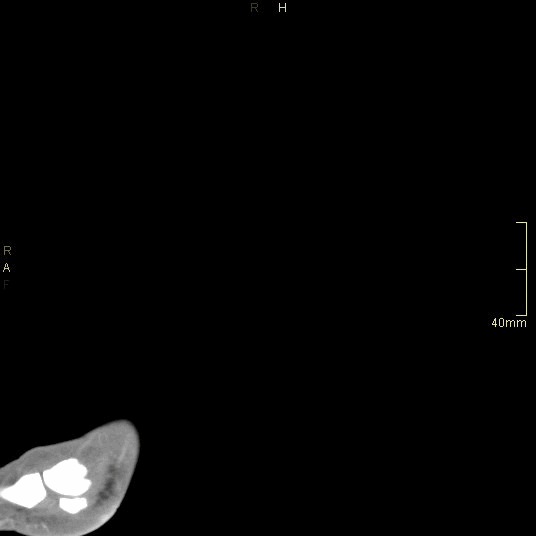

CT Ankle Contrast- Soft tissue window (sagittal)

CT Ankle Contrast- Bone window (sagittal)